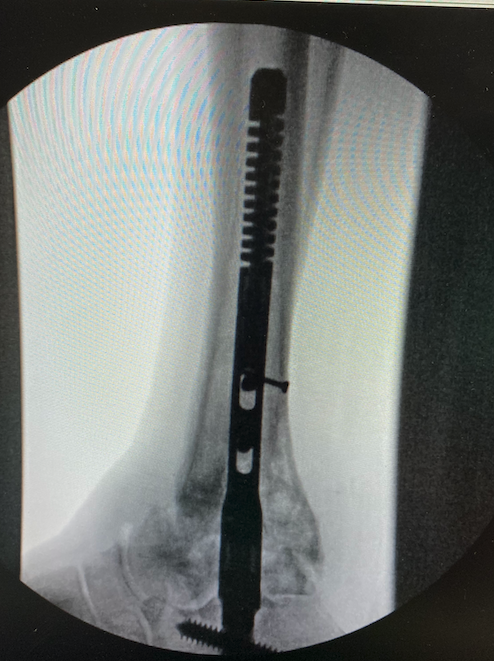

Phantom ActivCore™ Nail System (Paragon 28). This emerging option for tibiotalocalcaneal fusion and tibiocalcaneal fusion offers constant postoperative compression that accommodates up to eight mm of bone resorption across the joints, according to Paragon 28. They also share that the nail has an outer sheath with a proximal Flex Coil design and inner sliding core, with eleven different size options available. Specifically, the Flex Coil design contributes to stress sharing within the contoured anatomy of the tibia, says the company.

Byron L. Hutchinson, DPM, FACFAS who has used this nail since its launch several months ago, feels the stress-sharing feature within the tibia allows him to have less concern about possible tibial fracture, especially with longer nails.

According to the product website, the system’s reproducibility stems from the PRECISION® guide technology, which allows for precise placement of the initial drill pin, determining implant trajectory from distal to proximal. The parallel offset guide provides flexibility for surgeons to place an additional drill pin four mm in any direction if they prefer an alternate trajectory of the nail. The 7.2 mm threaded calcaneal peg offers variable angles of placement from zero to 18 degrees, improving bony purchase tailored to a patient’s anatomy.

Paragon 28 adds that surgeons implant the Phantom ActivCore nail through their carbon fiber Phantom® Ghost™ Outrigger apparatus. Its radiolucent inlay features allow surgeons to visualize the pegs’ direction and placement under fluoroscopy before they drill. Overall, the website adds that the Phantom Hindfoot TTC/TC System carries a comprehensive array of instrumentation for joint preparation in these cases, including cartilage removal tools, curettes, osteotomes, burrs, perforators and bone fenestration chisels.

“The nail can be used for a TTC fusion but also can accommodate a situation where there is no talus, such as a total ankle replacement (TAR) explant or diabetic Charcot where the talus is gone,” says Dr. Hutchinson, Medical Director of the CHI/Franciscan Advanced Foot and Ankle Fellowship in Federal Way, Washington.